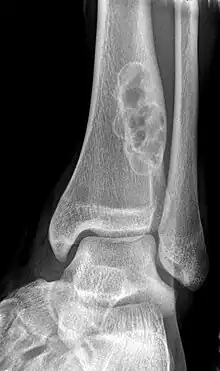

| X-ray of nonossifying fibroma of distal tibia. | |

Diagnosis is by X-ray or MRI, usually when investigating a person for something else.[2] Medical imaging typically shows a well defined radiolucent lesion, with a distinct multilocular appearance, sometimes looking like bubbles.[2] It is usually around 1–2 cm in size, but be as large as 7 cm.[3] They consist of foci consist of collagen rich connective tissue, fibroblasts, histiocytes and osteoclasts.[2] Usually no treatment is required.[1] Surgical curettage and bone grafting may be required if it is large.[3]

It is usually diagnosed by x-ray or MRI, when investigating another problem.[1] The tumor presents as a well defined radiolucent lesion, with a distinct multilocular appearance, sometimes looking like a "soap bubble".[5] If small and no symptoms, then biopsy is not needed.[1]